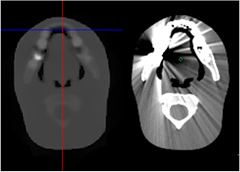

Whereas solving the range problem is a principal motivation of proton radiology and CT, it is not the only motivation. Early on, it was realized [19] that proton radiography potentially provides better density resolution and tissue contrast, compared to conventional x-ray imaging3, and more recent work appears to bear that out [20]. Proton radiography could also provide quick verification of patient setup in a cancer treatment facility, with very low radiological dose, and an appropriate radiography system might also be suited to real-time monitoring of the treatment beam [21]. Also, proton CT does not suffer from artifacts that often appear in reconstructions of x-ray CT scans, particularly as a result of metallic inserts (see section 6 and figure 14).

Computed tomography image reconstruction from x-ray projection data is a highly developed, mature field [61]. In general, the x-ray data, whether in cone-beam CT, helical CT, or multi-detector CT, are amenable to fast, efficient reconstruction by way of filtered back projections, but more general, more computationally intensive methods such as ART have also been well developed and are recognized to hold some advantages, such as yielding lower-noise images with fewer artifacts, especially at low radiation dose levels, and in regions with sharp changes in density, such as might be found around metallic inserts [62].